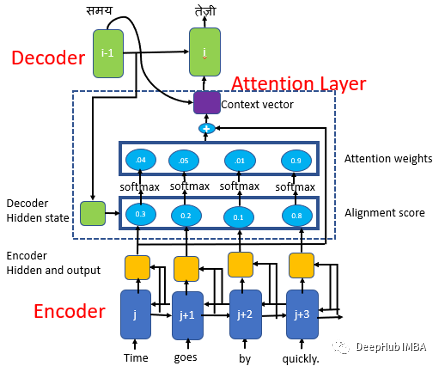

注意力机制

注意力模型也称为注意力机制,是一种深度学习技术,用于提供对特定组件的额外关注。注意力模型的目的是将更大、更复杂的任务简化为更小、更易于管理的注意力区域,以便按顺序理解和处理。

注意力模型的最初目的是帮助改善计算机视觉和基于编码器-解码器的神经机器翻译系统。该系统使用自然语言处理 (NLP) 并依赖于具有复杂功能的庞大数据库。使用注意力模型有助于创建固定长度向量的映射以生成翻译和理解。

注意力模型可以简单的分为3类:

-

自注意力模型

-

全局注意力模型

-

局部注意力模型

本文中我们将使用 Bahdanau 和 Loung 建议的论文中使用全局注意力模型(Global Attention Model)。

该模型基于与源位置和先前生成的目标词相关联的上下文向量来预测目标词。具有注意机制的Seq2Seq模型由编码器、解码器和注意层组成。